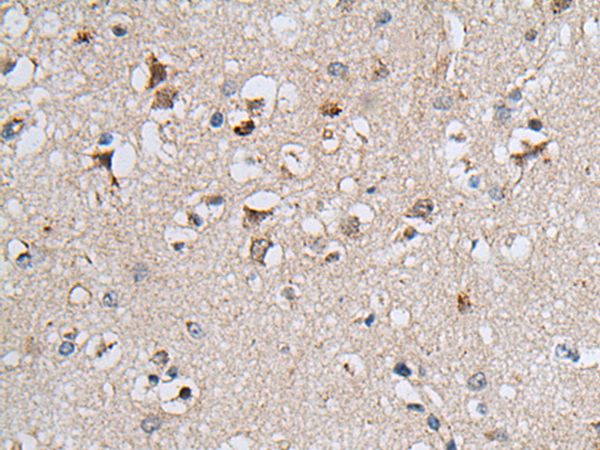

IHC positive control: |

Human colorectal cancer and human brain |

IHC Recommend dilution: |

25-100 |